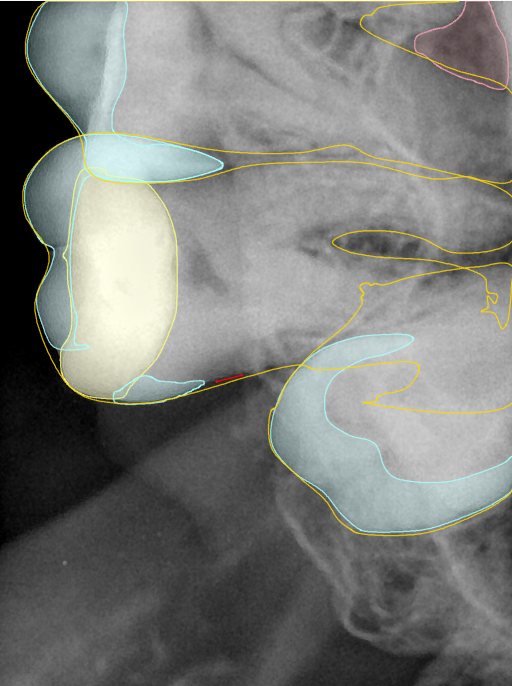

CR/DR 牙齿分割阶段记录

当前进展

- 完成了 CR/DR 牙齿相关分割训练

- 当前结果已经达到阶段预期,但仍有细节问题需要继续处理

相关测试

遇到的问题

- 训练过程中出现过 mask 下移问题

- 部分结果会出现 box 填充异常

- mask 边缘仍然有比较明显的锯齿感

参考

第二版算法问题测试